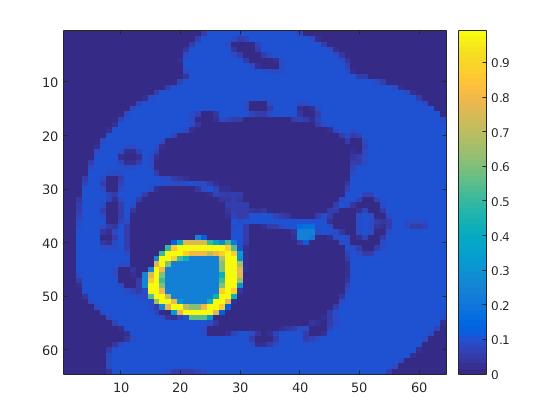

The first data set consists of a heart-shaped region and three circles on a static background (see figure 1 (a)). The two smaller circles are assumed to belong to

the same tissue type and therefore to the same subregion, which causes a total of four subregions, including the background. To simulate a more realistic application of dynamic SPECT

imaging, we used a synthesized representation of a rat liver as a second data set (see figure 1 (b)). The temporal concentration curves used to simulate the data sets

are shown in figure 2. As before, the total number of subregions was chosen to be equal to four in order to provide a both simple and realistic shape model.